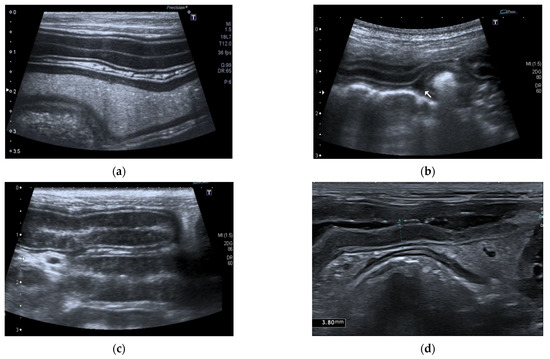

In 15/22 dogs (68%), the pancreas had a normal ultrasound appearance, with normal shape, margins, and echogenicity, homogeneous echotexture, and without pancreatic duct abnormalities (Figure 2).

Figure 2.

Ultrasound image of the right pancreatic limb with normal shape and echogenicity, regular margin, and homogeneous echotexture.

Conversely, 7/22 dogs (32%) had one or more of the anomalies described: two dogs had multiple hyperechoic spots in pancreatic parenchyma; one dog had inhomogeneous pancreatic echotexture with multiple hyperechoic spots; one dog had diffuse hyperechoic parenchyma with inhomogeneous echotexture and tortuous pancreatic duct; one dog had irregular margins and shape, hyperechoic parenchyma, and inhomogeneous echotexture; one dog had diffuse pancreatic heterogenicity, and one dog had irregular margins and tortuous pancreatic duct (Figure 3). The age of onset of symptoms in six of these seven dogs with abnormal parenchyma was greater than 4 years.

Figure 3.

Ultrasound image of right pancreatic limb: (a) Pancreas (between the caliper) with regular margin, homogeneous echogenicity, and mild inhomogeneous echotexture (b) Pancreas (between the white arrows) with regular margins (thickness 6.5 mm), normal echogenicity, and multiple point mineralizations (c) Pancreas (between the white arrows) with irregular margins (thickness 5 mm) multifocal hyperechogenicity, and inhomogeneous echotexture (d) Pancreas (between the white arrows) with irregular margin (thickness 4 mm), diffuse and severe parenchymal hyperechogenicity, and inhomogeneous echotexture.